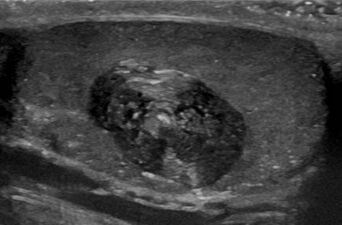

الكيسة الجلدية (إنگليزية: epidermoid cyst،[1] هي كيسة حميدة تتواجد عادة على الجلد. تنمو الكيسة إلى نسيج الأديم الظاهر. نسيجياً، تتكون الكيسة الجلدية من طبقة رقيقة من الخلايا الظهارية.

عادة ما تُشخص التكيسات الجلدية عندما يلاحظ الشخص نتوءًا على جلده ويسعى للحصول على رعاية طبية. يُجرى التشخيص النهائي بعد استئصالها بواسطة أخصائي علم الأمراض بناءً على المظهر المجهري للآفة الكيسية المبطنة للظهارة المتقرنة التي تحتوي على كيراتين مقرن تكلس. يمكن أيضًا رؤيتها على أنها آفات متساوية بواسطة التصوير بالرنين المغناطيسي أو فرط كثافة على FLAIR.

أشعة مقعطية توضح الحجم الكثيف المتجانس (شبيه لكيسة غير محددة).